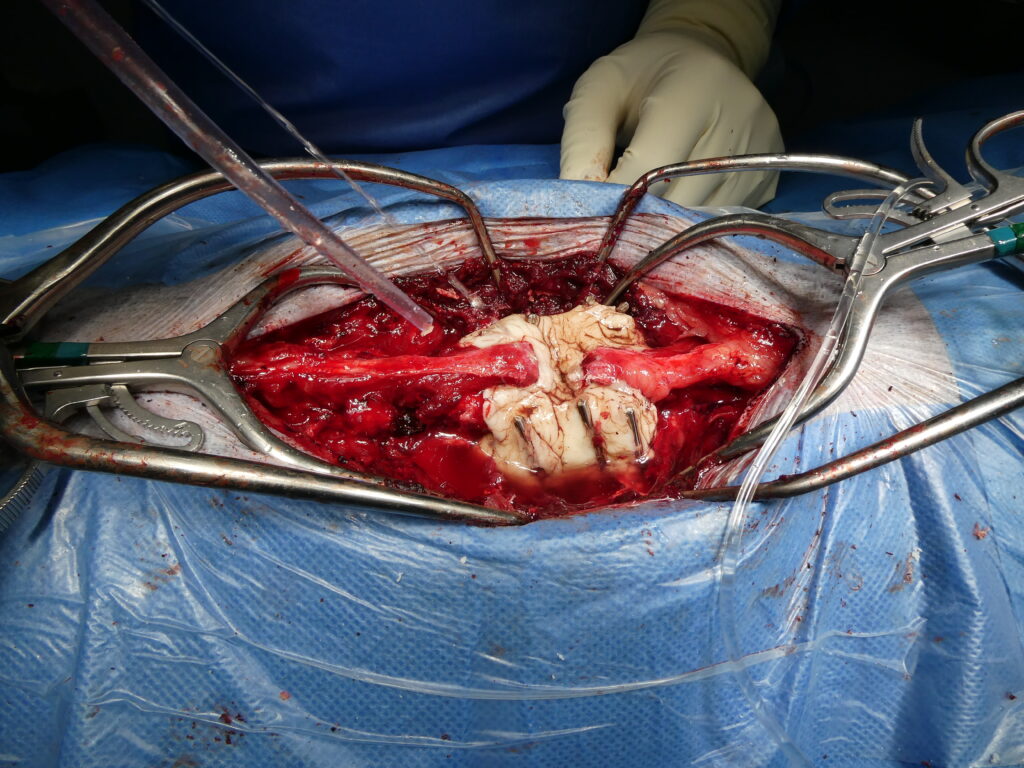

2026-01-01_182359

Exérèse d’une tumeur méningée thoracique chez un chat.

L’image de gauche correspond aux reconstructions scanner multiplanaires mettant en évidence une tumeur méningée thoracique responsable d’une compression médullaire sévère. Les flèches soulignent la prise de contraste intense et bien délimitée de la masse, ainsi que son effet compressif marqué sur la moelle épinière. L’aspect est typique d’une lésion extra-médullaire, clairement distincte d’une hernie discale, expliquant le tableau neurologique initial très grave avec paralysie complète de stade V.

L’image centrale illustre l’abord chirurgical peropératoire après exposition de la vertèbre concernée. Une laminectomie ciblée est réalisée afin d’accéder à l’espace épidural et à la lésion. Cette étape requiert une dissection extrêmement minutieuse, dans un environnement anatomique restreint, afin de préserver l’intégrité de la moelle épinière et des structures adjacentes.

L’image de droite montre l’aspect de la tumeur après ouverture osseuse et exérèse. La masse est individualisée puis retirée avec précision, permettant une décompression complète de la moelle épinière. Malgré la sévérité du déficit neurologique préopératoire, l’évolution clinique a été très favorable, avec une récupération fonctionnelle complète du chat après l’intervention, illustrant l’intérêt et l’efficacité de ce type de chirurgie neuro-oncologique lorsqu’elle est réalisée dans des conditions optimales.